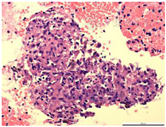

脑磁共振成像(MRI)显示双侧大脑半球、右丘脑、右颞下叶多发病变(图1A)。胸部CT图像显示纵隔和双肺门淋巴结肿大并伴有多个肺结节(图2A)。18f -氟脱氧葡萄糖(FDG)正电子发射断层扫描(PET/CT)显示右上颈部深淋巴结、门部、纵隔、多发肺结节、双侧髋关节肌间隙、左髋关节皮下软组织明显摄取FDG(图3)。超声(US)引导下左髋关节皮下软组织活检显示大量嗜酸性粒细胞及纤维血管增生,无法提供诊断线索。然后我们在局部麻醉下对纵膈淋巴结进行WANG™经支气管抽吸针。然而,标本中仅发现少量纤毛柱状上皮细胞,诊断仍不明确。最后在全身麻醉下行支气管超声引导下经支气管针抽吸(EBUS-TBNA)纵隔淋巴结,发现慢性肉芽肿性炎症,提示结节病诊断(图4)。

影像学难以明确诊断,需与细菌性脑脓肿、真菌性脑脓肿、胶质瘤、丘脑静脉性梗死及脑转移瘤等鉴别。确诊依靠支气管超声引导下经支气管针抽吸(ndobronchial ultrasound-guided transbronchial needle aspiration ,EBUS-TBNA)纵隔淋巴结,发现慢性肉芽肿性炎症,同时排除其他特异性感染后考虑结节病。